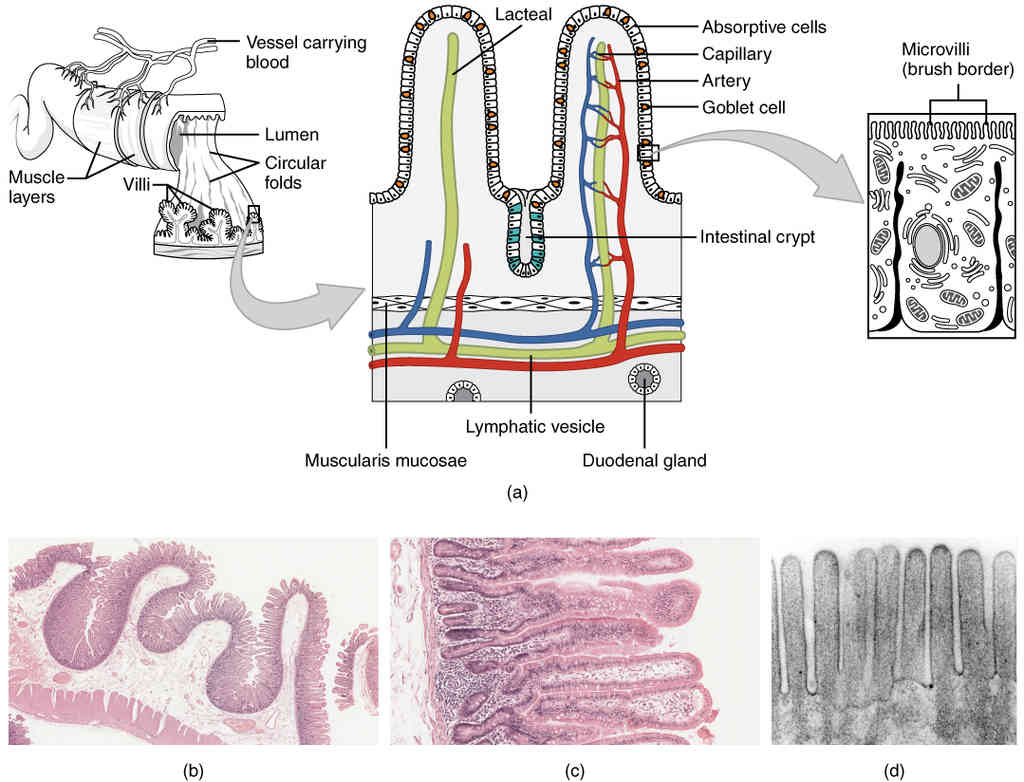

This page is under construction. For now, it is just a resource of the images found in the OpenStax Anatomy and Physiology Handbook. It wil slowly change into a revision tool. Each slide has a number. Use this to refer to the slide. When completed, it will have an unlabelled section, with labelled slides in parallel. On the unlabelled slides, write your answer and use the labelled slide to assess yourself. Keep track by also noting the number on each slide. Improvement at each attempt is important, more so than full marks on a first attempt.